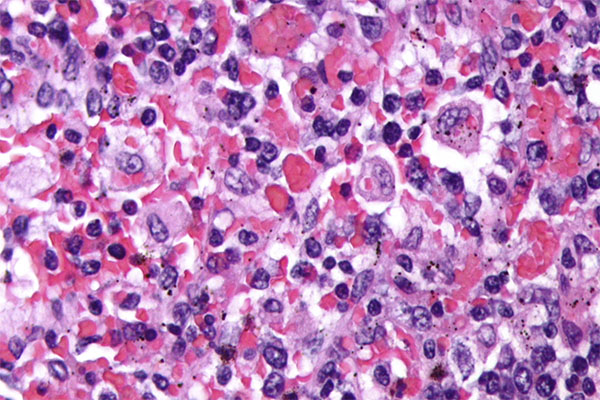

Según el CORDIS de la Comisión Europea, el emapalumab es un “medicamento huérfano” con el objetivo de cambiar drásticamente el tratamiento de la enfermedad y mejorar el pronóstico de los pacientes. La HLH se caracteriza por respuestas inmunitarias anómalas y por un estado de hiperinflamación que pueden estar debidas a un deterioro de la función de los linfocitos T citotóxicos, causado a su vez por mutaciones genéticas en la fase primaria de la enfermedad o por una enfermedad reumática, una infección o cáncer en la secundaria. Si no se detecta la aparición de la enfermedad en su fase primaria, cuando los niños son pequeños, es mortal. Tiene un 40% de mortalidad.